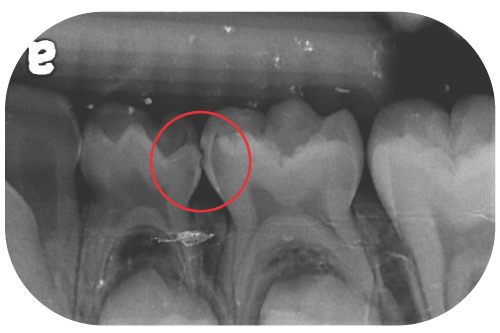

乳臼齒蛀牙已經非常靠近或已經碰到牙髓神經了

當蛀牙範圍已延伸到牙髓神經附近,此時小朋友常伴隨疼痛的症狀,必須先評估該顆牙剩餘齒質多寡、是否足夠支撐日後咀嚼功能?

如果可以,則進行牙髓切除術(俗稱的「抽神經」、「根管治療」)並搭配不鏽鋼牙套。